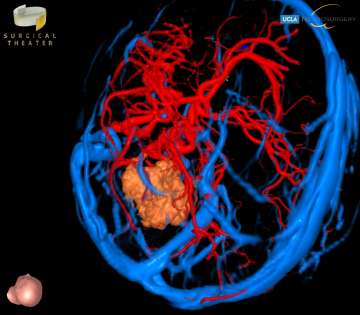

Choroid plexus tumors arise from the choroid plexus within the ventricles of the brain. These tumors are rare, representing only about 3% of brain tumors in children. About 10-20% of brain tumors found in the first year of life are choroid plexus tumors. The majority of choroid plexus tumors are either choroid plexus papillomas (CPP) or choroid plexus carcinomas (CPC). CPPs are benign and far more common, accounting for 80-90% of choroid plexus tumors. CPCs are malignant, and are more likely to spread to other parts of the brain and spinal cord. Symptoms for these tumors include headaches, nausea, lethargy, irritability, problems with development, and enlarged fontanelles. All of these are a direct result of the increased intracranial pressure and of the hydrocephalus that may be caused by the tumor. Surgical resection is the mainstay of treatment, but can be particularly complex in these cases, and should be performed by an experienced pediatric neurosurgery team.